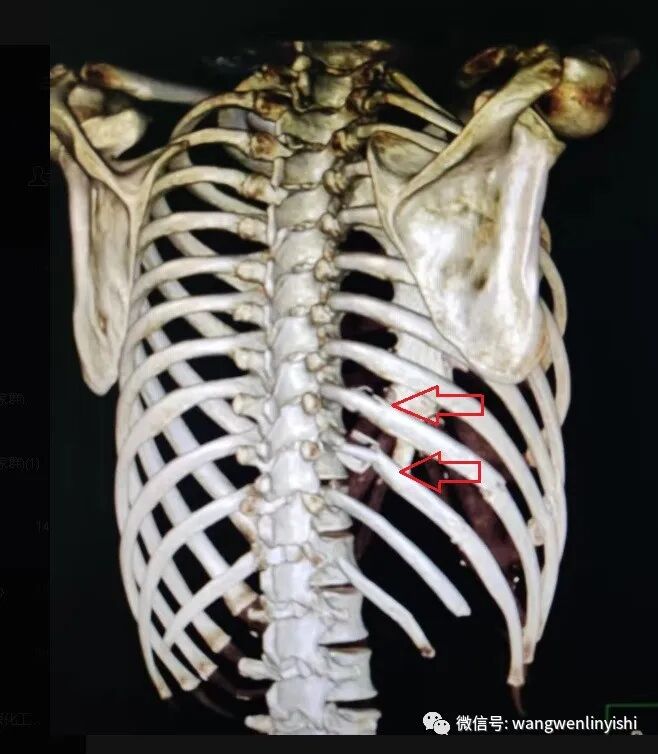

今天的患者为男性,35岁,因外伤3小时急诊入院。患者入院前3小时从高处坠落,右侧胸壁着地,伤后局部剧烈疼痛,呼吸时加重,伴呼吸困难。入院查体:右侧胸壁下部大面积皮肤擦伤,局部有明显压痛,骨擦感明显。右侧呼吸音明显减弱。身体其他部位未见外伤。术前行影像学检查,提示右侧第6、7、8、9、10肋骨骨折,所有五条肋骨在腋中线到腋前线之间均有一处骨折,全部离断,第9、10肋骨在后肋靠近脊柱旁均有粉碎性骨折,骨折端完全离断。右侧血气胸。术前诊断为重度胸外伤,肺裂伤,多根多处肋骨骨折,血气胸。

(右侧第9、10肋骨后肋粉碎性骨折,每条肋骨后肋都有两处骨折,中间部分完全离断)